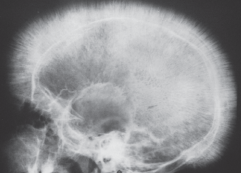

*Anemia induces release of erythropoetiin in thalassemia. Erythropoietin causes bone marrow to expand to compensate for decreased RBC function.